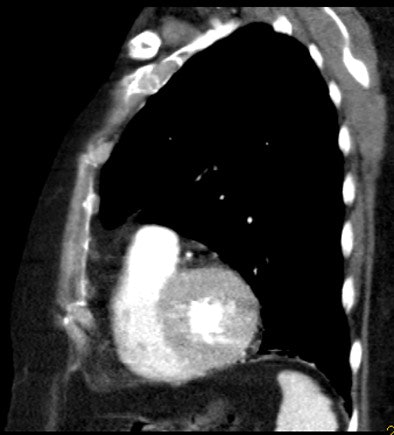

| An 81-year-old woman with acute chest pain and suspicion of acute pulmonary embolism. Short-axis images obtained at end-diastolic (above) and end-systolic (below) phase of the cardiac cycle using ECG-gated 16-slice CT. Right and left ejection fractions were measured at 43% and 41%, respectively. Note the variation of both ventricle volumes and myocardium thickness throughout cardiac cycle. On the same examination, slab MIP oblique reformatted images (bottom) revealed hypodensity in the right pulmonary artery and arteries of the right lower lobe consistent with acute pulmonary embolism. All images courtesy of Dr. Emmanuel Coche. |